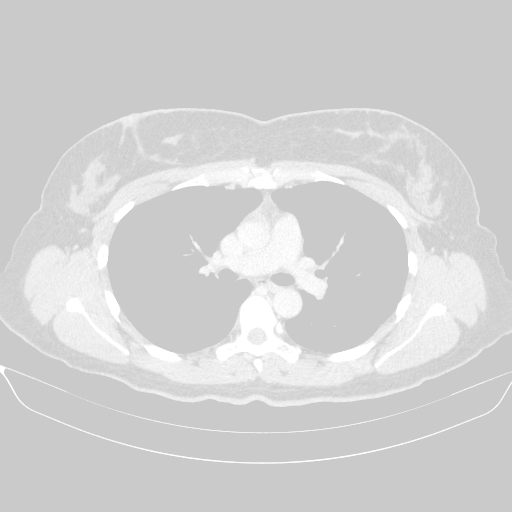

Reconstructed NATIVE CT scan (cycle consistency)

No window - Raw intensity values

Lung window (WL -600, WW 1500 β†’ Low βˆ’1350, High +150)

Mediastinum window (WL 40, WW 400 β†’ Low βˆ’160, High +240)